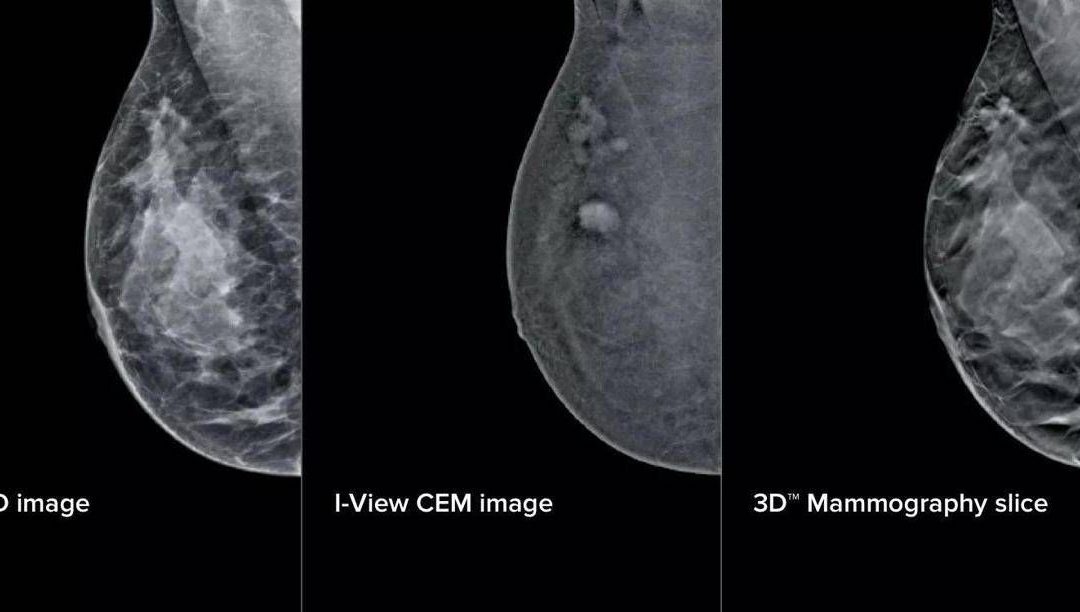

L’aggiornamento – illustra il San Camillo – si compone di elementi fisici e virtuali in due ambiti principali: la mammografia con refertazione e la biopsia mammaria. Sul fronte della refertazione, è stata introdotta una nuova workstation con monitor ad altissima risoluzione e strumenti avanzati di analisi delle immagini. Un software dedicato consente di valutare in modo oggettivo la densità del tessuto mammario, un elemento importante perché associato al rischio di tumore al seno. A questo si aggiunge un software che analizza struttura e densità del tessuto mammario, tecnologia di tomosintesi avanzata che riduce del 66% il numero di slice – le ‘fettine’ spesse 1 mm di tessuto mammario acquisite dal mammografo – mantenendo le stesse informazioni diagnostiche. Meno immagini da scorrere significa meno affaticamento: una riduzione del carico cognitivo per il radiologo stimata intorno al 13%, con benefici concreti soprattutto nelle sessioni di lettura multipla. A supporto dei medici – prosegue la nota – è stato integrato anche un sistema di intelligenza artificiale che evidenzia automaticamente le aree sospette sulle singole slice, come microcalcificazioni o alterazioni del tessuto, e fornisce indicazioni utili per la priorità di lettura. Studi preliminari indicano “un miglioramento della capacità di individuare lesioni fino al 9%”.

Sul fronte della biopsia mammaria, i mammografi di ultima generazione consentono di eseguire la procedura direttamente a partire da immagini con contrasto, unendo in un unico passaggio la localizzazione della lesione e il prelievo bioptico. Per la paziente questo si traduce in un percorso interamente nello stesso reparto, senza la necessità di ricorrere alla risonanza magnetica chiusa. Un apposito dispositivo meccanico permette inoltre di raggiungere anche le lesioni in posizioni difficili.